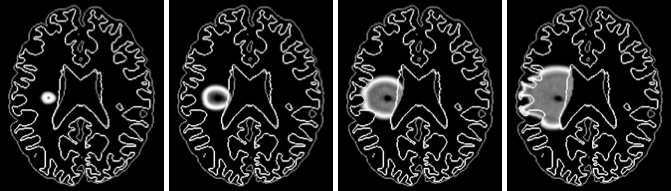

Gliome - reproduction d'une croissance logistique